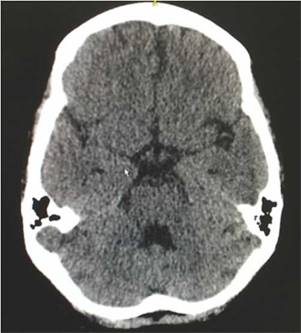

Ocho semanas después del egreso hospitalario presentó 2 episodios convulsivos tónico-clónicos, por lo que consultó otra vez al servicio de urgencias, realizándosele una punción lumbar que descartó neuroinfección, una tomografía cerebral simple que evidenció ligeros cambios atróficos corticales y microangiopáticos de pequeño vaso, además de una ligera dilatación del sistema ventricular (fig. 3). Se documentaron los siguientes resultados de laboratorio: complemento C3 de 77 mg/dl, complemento C4 de 18 mg/dl, creatinina sérica de 0,62 mg/dl, hemoglobina de 10,1 g/dl, leucocitos de 3.650 células y linfocitos de 820 células. El SLEDAI calculado en esta nueva hospitalización fue de 23. Se administró un nuevo esquema de metilprednisolona intravenosa de 250mg día por 3 días consecutivos, y posteriormente se continuó el esquema de prednisolona de 1 mg/kg por día que venía recibiendo y se decidió no suministrar manejo anticonvulsivante. Tuvo una evolución satisfactoria, sin nuevos episodios convulsivos con normalización clínica de la actividad lúpica y sin deterioro en la función renal, por lo que se dio egreso 10 días después de haber ingresado. Actualmente continúa en tratamiento con prednisolona en disminución progresiva de la dosis y con ciclofosfamida mensual, sin presentar nuevos eventos neurológicos ni episodios de dolor abdominal.